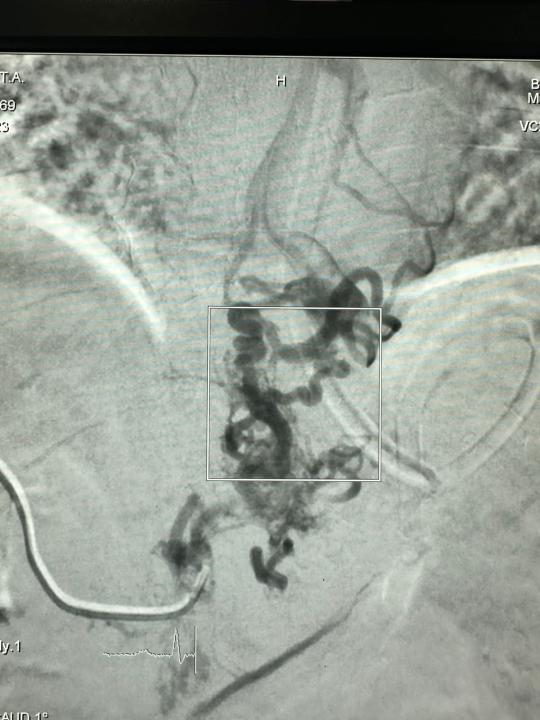

Данная высокотехнологичная операция называется ретроградная трансвенозная облитерация с использованием спиралей (CARTO — Coil-assisted retrograde transvenous obliteration).

Ретроградная трансвенозная облитерация вен с помощью спиралей (CARTO) является современным, безопасным и эффективным вариантом лечения портального гипертензивного варикозного кровотечения, используемый интервенционными радиологами. Процедура включает в себе блокировку расширенных вен при помощи спиралей, специального клея и эмболов, что снижает риск их разрыва. Операция проводится под местной анестезией, с применением ангиографической установки. Подобные дорогостоящие операции проводятся для пациентов бесплатно за счёт средств системы медицинского страхования.